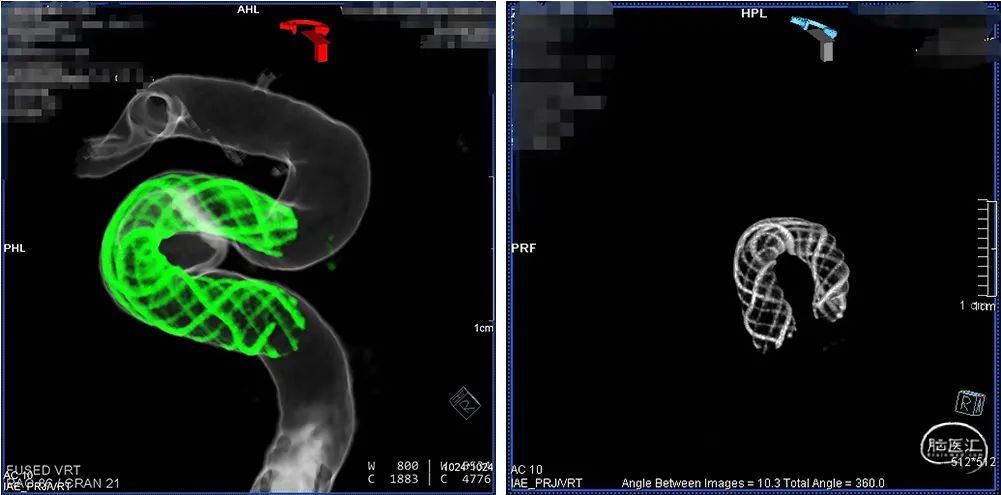

释放支架头端,远端锚定后,确认支架远端释放,贴壁良好,缓慢采用推挤方式将支架释放。

支架成功释放后,造影显示动脉瘤瘤颈支架覆盖贴壁良好,右侧颈内动脉通畅,右侧颈内动脉及分支血管显影良好,无血栓。

术中快速CT扫描未见颅内出血,支架贴壁良好。

1.本病例为海绵窦段宽颈动脉瘤,血管管腔相对粗,且血管迂曲,传统支架金属覆盖率低,网眼相对较大,贴壁性较差,治疗难以达到理想的栓塞效果。Nuva®血流导向密网支架操作简便,术中释放顺利,30%-35%的金属覆盖率起到显著的血流导向作,有利于管腔重建,提高治愈率。

2.Nuva®血流导向密网支架输送系统的释放-回收段显影设计,术中可准确快速指示出释放-可回收区域,区间显影设计极大地方便了术中的操作,有助于支架的成功释放。

3.Nuva®血流导向密网支架具有较好的柔顺性,释放于迂曲的血管中,可以很好地顺应血管形态,术中打开顺畅,贴壁良好,径向支撑力适中,推挤过程也不易折弯变形;支架整体显影设计,透视效果优异,术中很容易观察支架的打开、走形及贴壁情况。